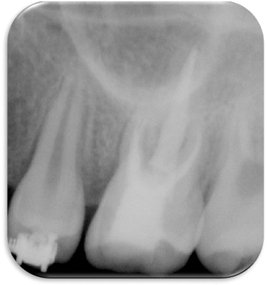

Figure 2

Pre-operative periapical x-ray.

Figure 2 Pre-operative periapical x-ray.